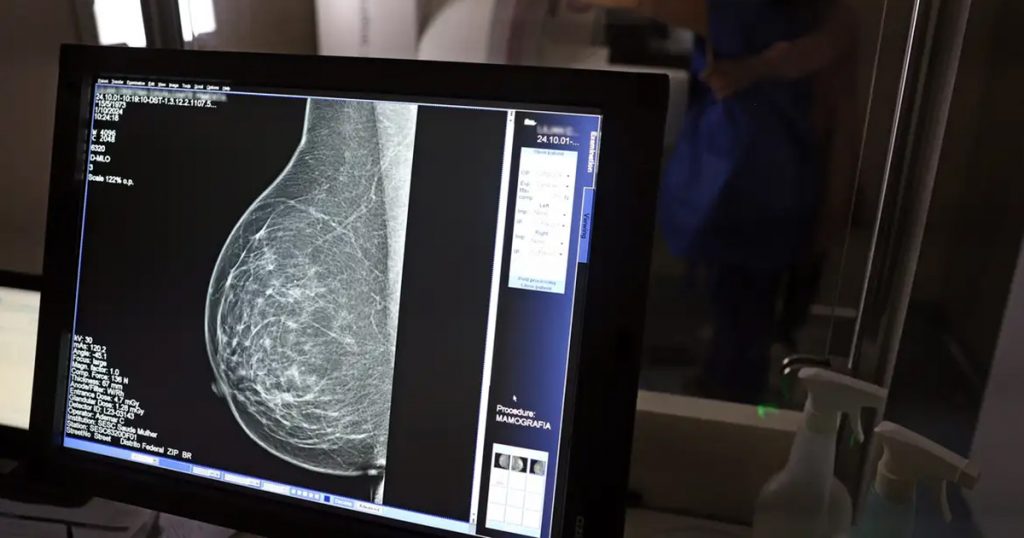

Um novo dispositivo para exames das mamas, que utiliza micro-ondas em vez de radiação ionizante, está sendo desenvolvido por pesquisadores da Escola Politécnica (Poli) da Universidade de São Paulo (USP) e do Instituto Federal de São Paulo (IFSP). Ainda em fase de protótipo, a tecnologia promete ser uma alternativa menos dolorosa e mais acessível à mamografia tradicional.

Sanches comenta ainda a respeito da importância da mamografia e de ser um exame presente em todo o país: “A gente fica muito feliz de colocar o Brasil no mapa dos seletos países que têm essa tecnologia. São bem poucos. Hoje em dia a mamografia é uma tecnologia que pode ser muito benéfica”.